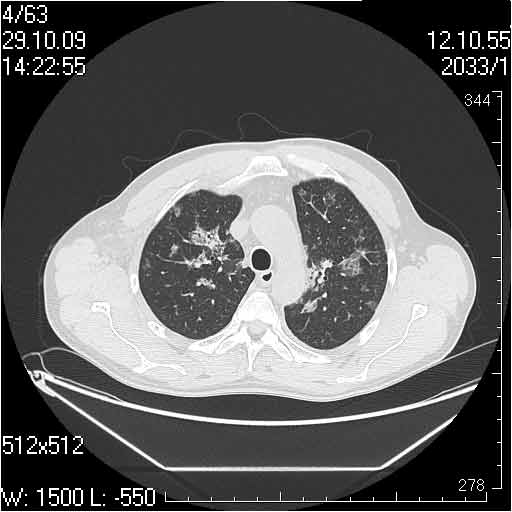

Случай №1

Женщина 50 лет.

Случай 1: изменения характерны для интерстициальной пневмонии (IIP/UIP idiopathic interstitial pneumonia/usual interstitial pneumonia); говорить о конкретной форме без открытой биопсии затруднительно.